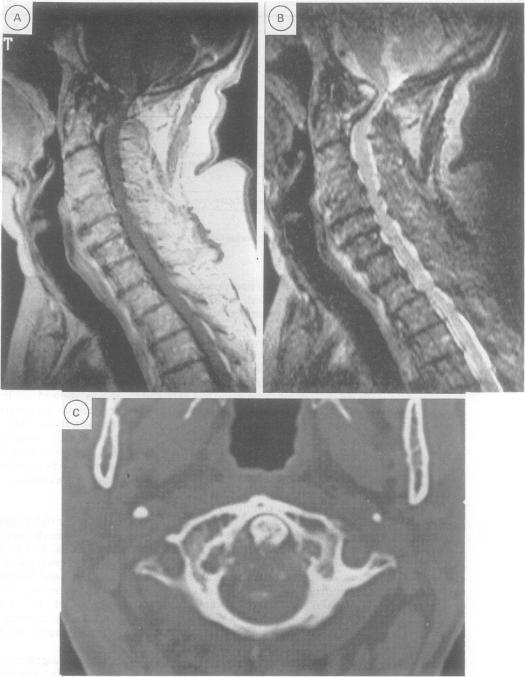

An extradural mass at the craniocervical junction causing progressive neurological disability in five elderly patients is described. The lesion, which might be confused with a meningioma or other tumour, is composed of amorphous degenerate fibrocartilaginous material and could be due to degeneration of the ligaments responsible for atlanto-axial stability. Recognition of the condition early is important as the patient's clinical condition will deteriorate without decompression. Anterior transoral removal is relatively simple, unlike surgery for tumours in the area, and will not destabilise the craniovertebral junction. It is likely that a proportion of these lesions are undetected, misdiagnosed or untreated to the detriment of the patient.